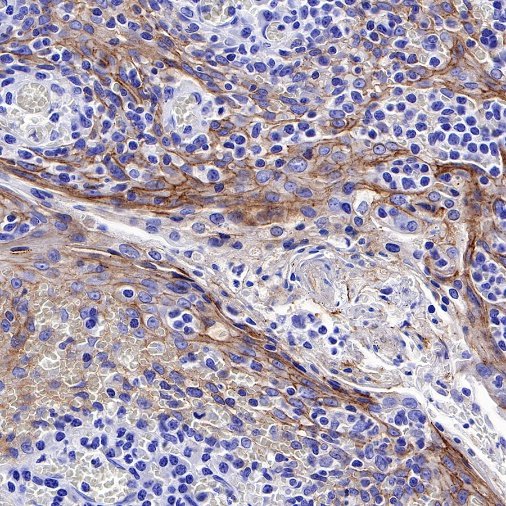

| IHC-P |

1:500 |

null |

Nectin-4 (Nectin cell adhesion molecule 4) is a type I transmembrane cell adhesion molecule belonging to the Nectin family. A homolog formerly known as the poliovirus receptor (PVR/CD155) is also known as the poliovirus receptor associated (PRR) protein. During physiological development, Nectin-4 is specifically expressed during embryonic and fetal development and is very low expressed in adult tissues. It forms physical connections between neighboring cells and is essential for enabling intercellular communication, migration, and other important cellular processes.

Nectin-4 is overexpressed in a variety of tumor cells, and Nectin-4 is used as a marker for cancer recurrence and metastasis, which is associated with poor prognosis of a variety of cancers, including uroepithelial carcinoma, breast cancer, ovarian cancer, pancreatic cancer, non-small cell lung cancer, gastric cancer, hepatocellular carcinoma and bladder cancer. Nectin-4 can promote tumor cell proliferation and differentiation, angiogenesis, lymphangiogenesis and lymphatic metastasis through activation of PI3K/AKT pathway, playing an important role in the occurrence and metastasis of cancer. Nectin-4 is also an independent biomarker associated with poor overall survival in some cancer types. Due to its high specific expression in tumors, drug studies targeting this target have emerged.